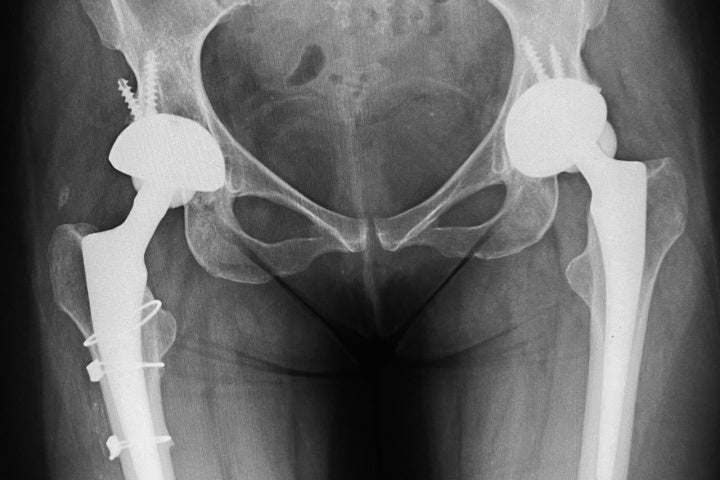

Em 2016, Isabel já se encontrava em uma cadeira de rodas devido ao comprometimento completo de seu quadril por osteoartrite. Ela passou por duas cirurgias, ambas para a implantação de próteses no quadril (bilaterais). A primeira cirurgia, realizada em janeiro, foi extremamente complicada, com um incidente durante a colocação da prótese que resultou em uma reabilitação de vários meses. Em outubro do mesmo ano, ela enfrentou o mesmo procedimento no lado esquerdo.

Recentemente, devido a um movimento errado a prótese do lado esquerdo quebrou. Isabel não possui plano de saúde e a prótese oferecida pelo Sistema Único de Saúde (SUS) é indicada apenas para idosos devido à sua durabilidade limitada. No setor privado, o pagamento deve ser feito à vista, sem opções de parcelamento.

O médico confirmou que a prótese de cerâmica era necessária e explicou que, devido à natureza da cirurgia, não era possível apenas substituir a peça quebrada; todo o dispositivo precisaria ser trocado.

Essa cirurgia é invasiva, pois se alguma parte estiver cimentada, é necessário abrir o osso para remover e substituir, tornando-a uma intervenção significativa. Até o momento, ainda não houve uma decisão sobre a realização da cirurgia.